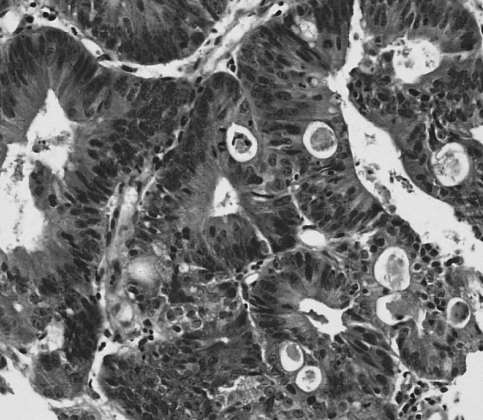

Figure 3

Histopathology showed malignant, small, round cells with prominent nuclei but scanty cytoplasm (H&E stain, ×400).